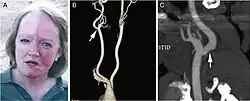

Harlequin syndrome, also known as "harlequin sign", is a condition characterized by asymmetric sweating and flushing on the upper thoracic region of the chest, neck and face. Harlequin syndrome is considered an injury to the autonomic nervous system (ANS). The ANS controls some of the body's natural processes such as sweating, skin flushing and pupil response to stimuli.[1] Individuals with this syndrome have an absence of sweat skin flushing unilaterally, usually on one side of the face, arms and chest. It is an autonomic disorder that may occur at any age.[2]

Symptoms associated with Harlequin syndrome are more likely to appear under the following conditions: vigorous exercise, warm environments and intense emotional situations. Since one side of the body sweats and flushes appropriately to the condition, the other side of the body will have an absence of such symptoms.[3]

The "Harlequin sign" is unilateral flushing and sweating of the face, neck, and upper chest usually after exposure to heat or strenuous exertion.[6] Horner syndrome, another problem associated with the sympathetic nervous system, is often seen in conjunction with harlequin syndrome.

Since Harlequin syndrome is associated with a dysfunction in the autonomic nervous system, main symptoms of this dysfunction are in the following: Absence of sweat(anhidrosis) and flushing on one side of the face, neck, or upper thoracic area. In addition, other symptoms include cluster headaches, tearing of the eyes, nasal discharge, abnormal contraction of the pupils, weakness in neck muscles, and drooping of one side of the upper eyelid.[3]